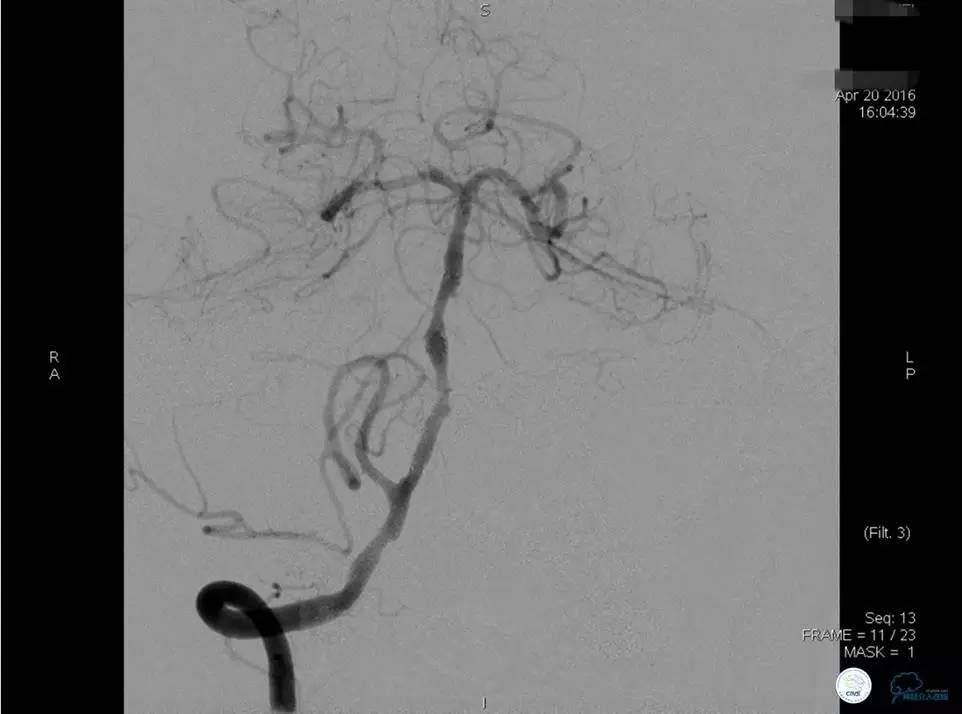

▼DSA示右侧椎动脉发育低下,弥漫性狭窄,可以看到左侧椎动脉反流,因此判断左侧椎动脉V4段CTO。

微导丝穿过闭塞段,微导管造影,球扩闭塞段,置入Wingspan支架,血流完全恢复正常。

患者术后2天再次出现卒中发作,药物治疗好转,此后病情稳定。半年后复查DSA,见支架闭塞,侧支循环开放。患者一般情况好,mRS:1分。